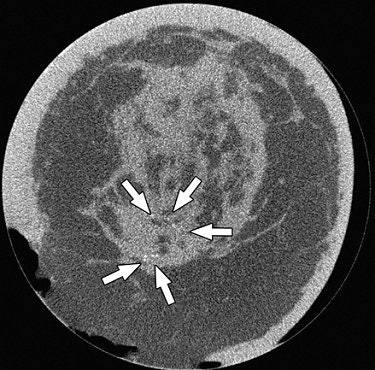

| Breast CT shows an ill-defined mass (ductal carcinoma in situ [DCIS]). Image courtesy of John Boone, Ph.D. |